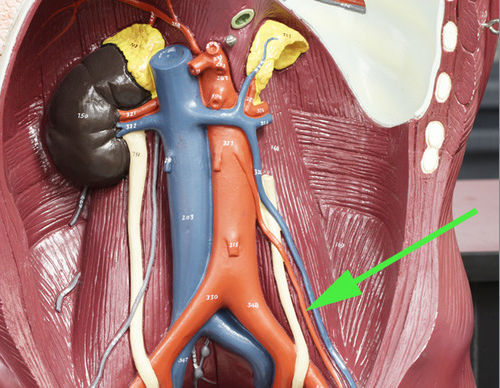

what is the green arrow pointing at? //abdominal aorta

In this unsexed model of the human blood vessels, the green arrow is indicating the

genital/gonadal artery.

In this model of human blood vessels, the green arrow is marking the external iliac artery.

In the area marked by the green arrow, the aorta is called the thoracic aorta